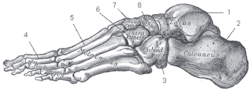

Squelette

Le squelette du pied est constitué de trois parties, d'arrière en avant : le tarse, le métatarse et les phalanges. Le tarse est constitué de sept os courts que l'on peut répartir en deux groupes : en arrière, le calcanéus (ou calcanéum) et le talus (ou astragale) ; en avant, l'os cuboïde, l'os naviculaire (ou scaphoïde tarsien) et les trois os cunéiformes (latéral, intermédiaire et médial). Les cinq métatarsiens sont des os longs qui forment le métatarse et relient l'os cuboïde et les trois cunéiformes aux phalanges des orteils.

On peut aussi diviser le pied selon une autre approche : l'arrière-pied, constitué du talus et du calcanéus ; le médio-pied, constitué de l'os cuboïde, de l'os naviculaire et des os cunéiformes ; l'avant-pied, constitué des métatarsiens et des phalanges.